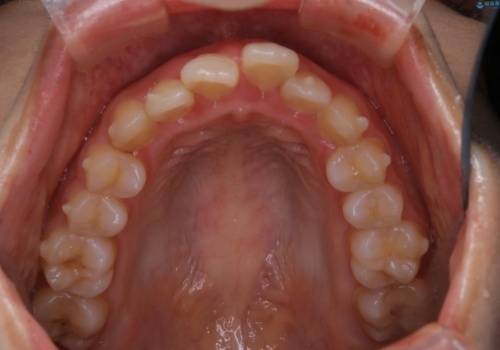

- 治療計画

- 4年ほど前から地元の歯科医院にてインビザライン治療を行っていたが、引っ越し後に通いづらくなってしまったため、治療が途中で止まってしまっているとの事で来院されました。性格的にインビザラインの継続した使用が難しいとのことで、ワイヤー装置にて最終仕上げを行いました。